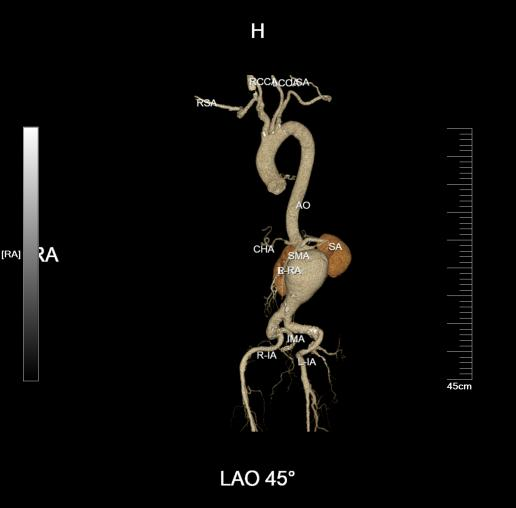

患者因出现左胸腹部疼痛至当地县医院就诊,提示腹主动脉瘤,后转至市人民医院就诊,急诊收住肝胆胰外科二病区(血管外科、介入科)。肝胆胰外科团队为其完善相关检查,其中胸腹部CTA检查提示:腹主动脉下段可见巨大瘤样扩张,直径约75mm,双侧髂总动脉管腔扩张。

腹主动脉瘤体巨大、瘤颈较短,手术难度大,在术前充分研讨、准备后,科室特邀专家工作站专家云南省第一人民医院血管外科龚昆梅主任现场指导手术。

手术采取“腹主动脉瘤切除+人工血管置换术”的方式,通过全麻下开腹暴露腹主动脉瘤,阻断病变段主动脉血流后切除瘤体,用人工血管与正常血管断端吻合,重建血流通道。